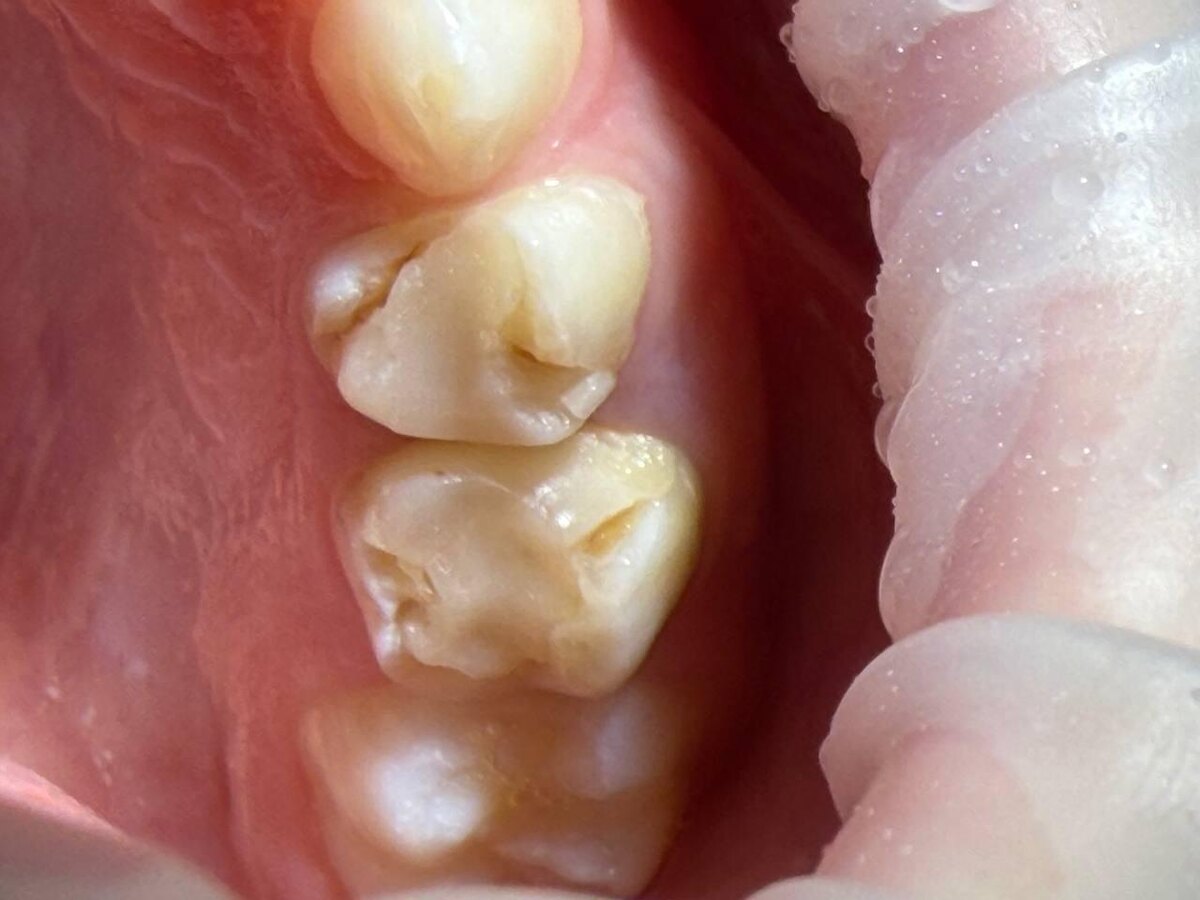

👆 На фото выше как раз пример работы без изоляции коффердамом. Нарушение краёв пломбы, вторичный кариес, разрушение вокруг реставрации. Что такое коффердам рассказывала в этом посте.

Раньше даже существовала легенда, мол у детей пломбы часто выпадают - это нормально. Но со временем начали изучать причины и стало понятно, почему это происходит:

1. У детей в 2 раза сильнее слюноотделение, чем у взрослых. Полимерные пломбы очень чувствительны к влаге. Даже небольшая влажность может нарушить адгезию, и пломба просто не будет держаться долго.